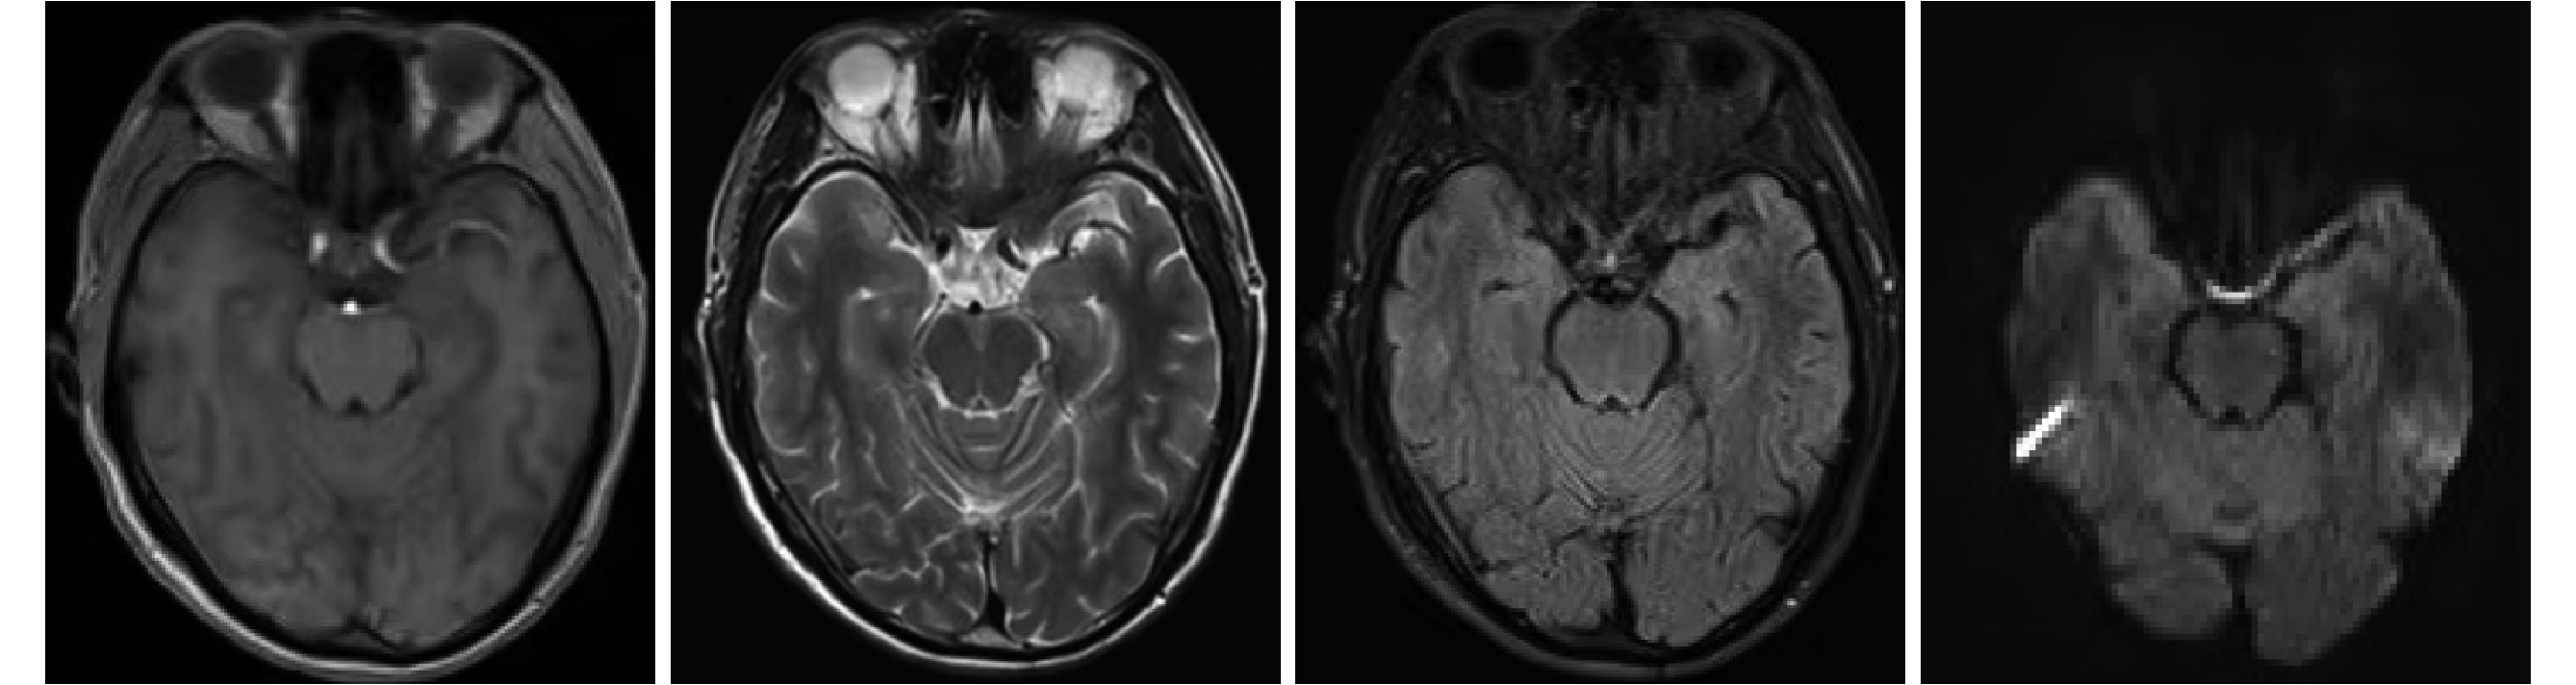

入院體格檢查:血壓 133/70 mm Hg(1 mm Hg=0.133 kPa);神清,語利,高級神經活動正常;雙側瞳孔等大等圓,直徑約 3 mm,對光反射靈敏,雙眼球活動自如,無眼震及復視,余顱神經(-),四肢肌力Ⅴ級,四肢肌張力正常,四肢腱反射(++);深淺感覺正常;雙側指鼻試驗、跟膝脛試驗穩準;雙側病理征陰性,Romberg 征陰性,腦膜刺激征陰性。輔助檢查:2021 年 3 月 23 日顱腦增強 MRI 平掃+彌散加權成像檢查(圖1)示雙側額頂葉缺血灶,腦白質變性(非特異性病變,與腦膜腦炎無明顯關系)。

圖1

2021 年 3 月 23 日頭顱增強 MRI+彌散加權成像

雙側額頂葉缺血灶,腦白質變性,未見腦膜腦炎特殊征象